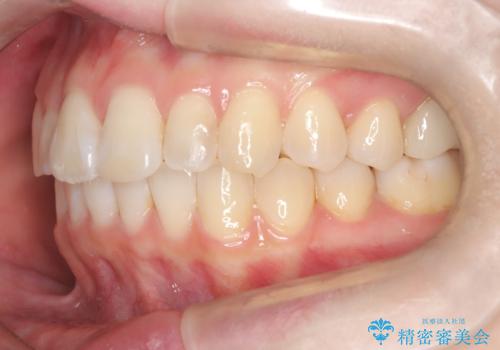

前歯のガタつきをマウスピース矯正で改善

- 前歯のガタツキが気になると来院されました。

奥歯の噛み合わせは綺麗に噛んでいたため、前歯の叢生(でこぼこ)に集中して治療するように計画しました。